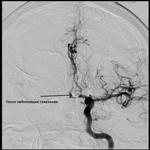

Разрывы артериальных аневризм головного мозга в 50% случаев являются причиной субарахноидальных кровоизлияний. Это заболевание дает высокую летальность в первые две недели, чаще встречается у людей молодого и среднего возраста. Все это определяет не только медицинскую, но и социально-экономическую значимость данной патологии. Смертность к 30–му дню от момента возникновения САК из аневризмы достигает 45%, а 30% выживших становятся инвалидами. В 2–4% случаев повторное кровоизлияние происходит в первые 24 часа, а в 15–20% – в первые две недели. При наличии неврологической симптоматики (паралич черепных нервов, нарушение деятельности ствола мозга) риск разрыва аневризмы особенно велик (до 6% в год), поэтому таких пациентов необходимо регулярно обследовать и лечить. Лечение артериальных аневризм головного мозга в остром периоде субарахноидального кровоизлияния является одной из наиболее сложных проблем современной нейрохирургии. Существует три подхода к тактике ведения больных с внутричерепными аневризмами: динамическое наблюдение, трепанация черепа с наложением клипсы (клипирование) и эндоваскулярная окклюзия аневризмы микроспиралями (эмболизация). Эндоваскулярное лечение артериальных аневризм головного мозга является эффективным методом лечения больных с субарахноидальным кровоизлиянием. В публикациях, описывающих применение методов эндоваскулярного лечения артериальных аневризм в остром периоде субарахноидального кровоизлияния, отмечаются хорошие результаты внутрисосудистых вмешательств (образование устойчивого тромба на микроспиралях) и снижение процента летальности до 9-12 %. 01.08.2012 впервые в БСМП проведен мастер – класс с участием специалиста из МКДЦ Володюхина М.Ю. по эндоваскулярной эмболизации аневризм сосудов головного мозга. Было прооперировано двое больных (42 и 45 лет). У пациентки Х. ,45 лет, в «холодном» периоде разрыва аневризмы передней соединительной артерии (ПСА) выполнена тотальная эмболизация аневризмы спиралями. Второй пациент, Г., 42 лет, поступил в БСМП 01.08.2012 с субарохноидальным кровозлиянием в остром периоде. После комплекса необходимых обследований пациент доставлен в операционную. Ему также выполнена эндоваскулярная эмболизация аневризмы передней соединительной артерии (ПСА). Технически обе операции выполнены успешно, с хорошим ангиографическим результатом. Оба пациента находятся под наблюдением неврологов, нейрохирургов и эндоваскулярных хирургов. Эндоваскулярные вмешательства при аневризмах церебральных сосудов, внедренные в БСМП, выводят технологии лечения пациентов нейрохиругического профиля на качественно новый этап.